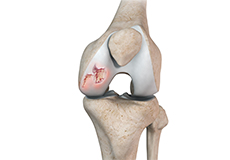

Chondral or Articular Cartilage Defects

The articular or hyaline cartilage is the tissue lining the surface of the two bones in the knee joint. Cartilage helps the bones move smoothly against each other and can withstand the weight of your body during activities such as running and jumping. Articular cartilage does not have a direct blood supply to it, so has less capacity to repair itself.